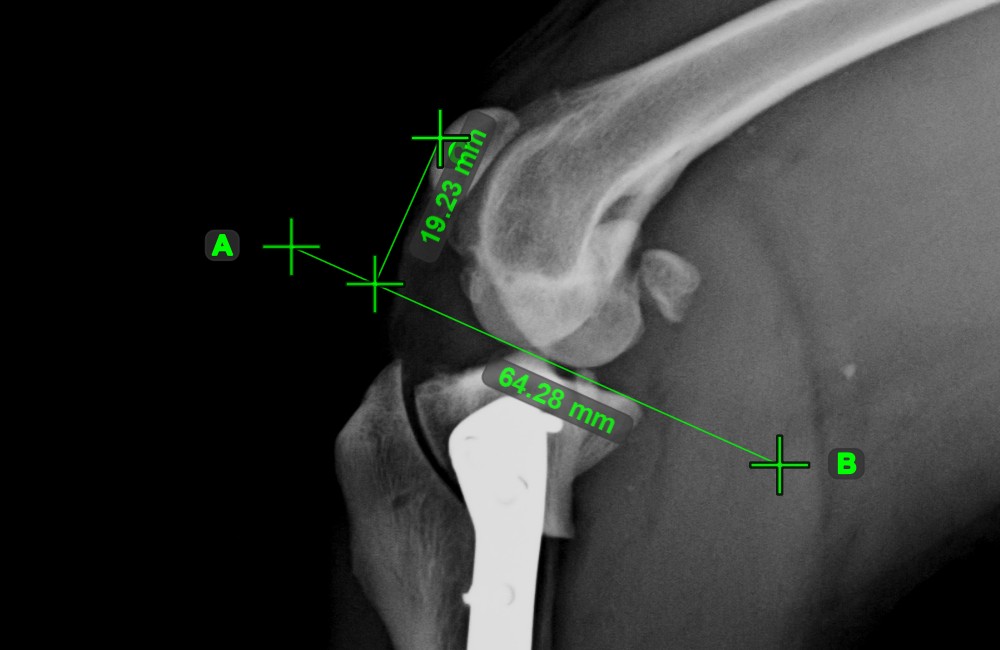

Erstellen Sie eine Linienmessung, um den Abstand zwischen zwei Punkten mit hoher Genauigkeit zu berechnen.

Wählen Sie das Werkzeug Linienmessung aus und weisen Sie es einer der verfügbaren Maustasten zu. Setzen Sie die Start- und Endpunkte in der Szene oder wählen Sie sie aus bereits vorhandenen Punkten im Bild aus. Der Abstand zwischen den beiden Punkten wird automatisch anhand der Standardkalibrierdaten oder der durch die Längenkalibrierung-Messung neu kalibrierten Daten berechnet.

Ändern Sie den Start- und Endpunkt mit dem Werkzeug Objekt auswählen/verschieben. Der Abstand zwischen den beiden Punkten wird automatisch neu berechnet.